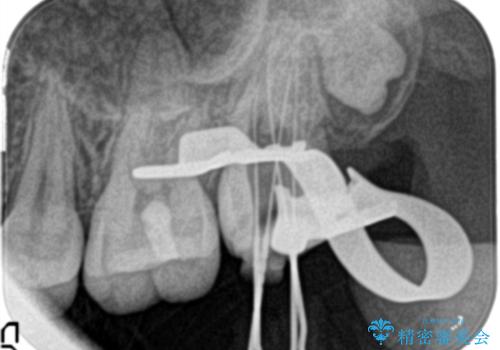

- 他院にて奥歯の治療をしても痛みが引かずに、ラバーダムの存在を知り、無菌的な治療を行える病院を探して当院を受診されました。

根管治療~フルジルコニアクラウンにて修復しております。

治療前には打診、圧痛がありましたが治療後には症状が消失し、3ヶ月後のレントゲンでも透過像の縮小を認めています。

治療介入時、根管内部にはカリエスや異物が存在する状態でしたが適切な処置を行うことで症状を改善することができました。